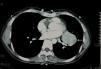

Se trata de una paciente de 41 años de edad, de nacionalidad china, que tras un cuadro de tos seca comienza de forma aguda con dolor torácico1 izquierdo y disnea de esfuerzo. Ante dicha clínica acude a urgencias, donde se realiza radiografía de tórax, que revela la presencia de una masa pulmonar infrahiliar izquierda (fig. 1). La PET-TC muestra una masa infrahiliar de 59×42×50mm (fig. 2) y 7 nódulos pulmonares de entre 1 y 12mm. Ni la masa ni los nódulos presentan actividad metabólica incrementada. Se procede a exéresis íntegra de la masa por neumotomía. Como complicación aislada presentó hemotórax en el postoperatorio y fue necesaria una reintervención quirúrgica, con evolución posterior satisfactoria, y pudo ser dada de alta a domicilio a las 72h de la primera intervención. La histología confirma un neumocitoma de 65mm de diámetro máximo, de patrón mixto, con predominio sólido con áreas pseudopapilares, con ausencia de atipia, mitosis o necrosis2. Fueron necesarias 2 intervenciones quirúrgicas para resecar la totalidad de los neumocitomas, pues presentaba, además del descrito, otros 7 neumocitomas, de menor tamaño, de entre 1 y 12mm, distribuidos en el lóbulo inferior izquierdo, el lóbulo superior izquierdo y el lóbulo inferior derecho.